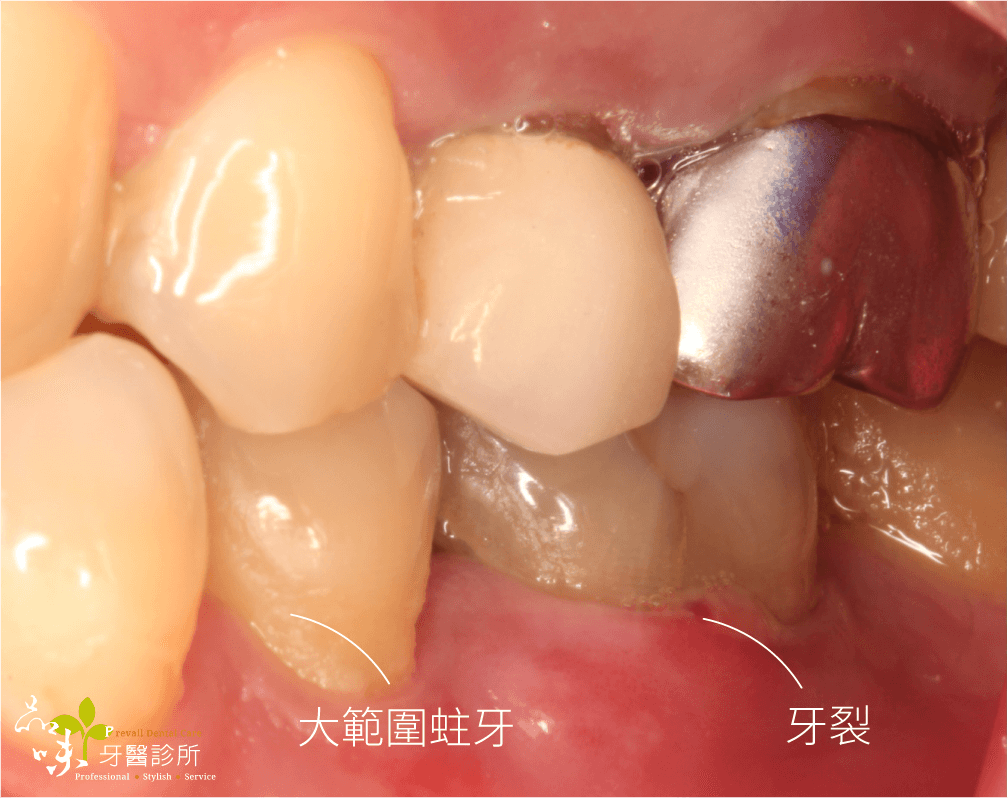

下午診間走進一位牙齒劇烈疼痛的陳先生(化名)。左手捧著下巴,疼痛難耐地說:「醫師,今天不小心咬到骨頭,現在只要一喝水就感到抽痛,痛到無法咬東西,請問這顆牙怎麼辦?」

經過臨床檢查後,我發現這顆牙已呈現牙根斷裂的狀況,依目前醫療常規只能把斷裂的牙齒拔除。

文首提到牙裂的陳先生,當天下午就安排了手術。在一系列數位資料蒐集後,進行藍光導航植牙。傍晚陳先生的牙齒就不疼了。